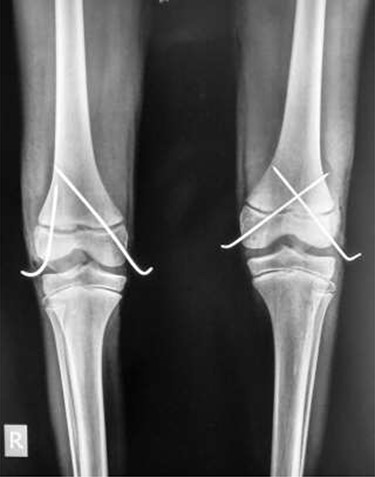

Follow-up was every 6 months over the next 5 years (Fig. 4A and B). Full range of motion was achieved in both limbs, with the child fully ambulatory and with no leg-length discrepancy. Future adult femur length does not appear to have been impacted.

(A) Frontal and lateral view of right knee at 6-months post-injury; (B) frontal and lateral view of left knee at 6-months post-injury

As it was a bilateral injury, gentle physiotherapy was started after plaster removal—only active and assisted-active movement was used, rather than force. Other studies have encouraged early physiotherapy post-plaster removal to reduce the risk of fixed-flexion deformity [3]—some suggest caution in using forcible manipulation for deformity correction [1]. The patient’s recovery has been excellent (Fig. 4A and B); long-term results demonstrate a full range of movement bilaterally with no distal neurological deficits. The patient can walk unassisted, has been observed running and is reportedly back to all routine activities.